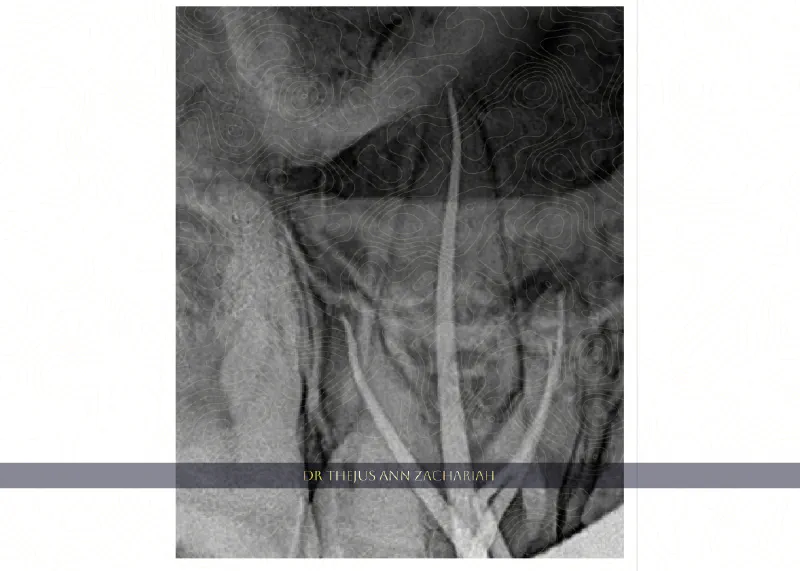

Root Canal Treatment

RCT - 48RCT - 48 RCT - Upper Molar With MB2 - 16RCT - Upper Molar With MB2 - 16 RCT - Through Crown 36RCT - Through Crown 36